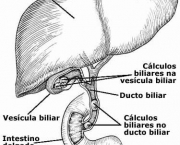

Além de sintetizarem proteínas, as células hepáticas são responsáveis também pela metabolização de substâncias como o álcool, a grande maioria das drogas, e também é responsável pela produção da bílis.